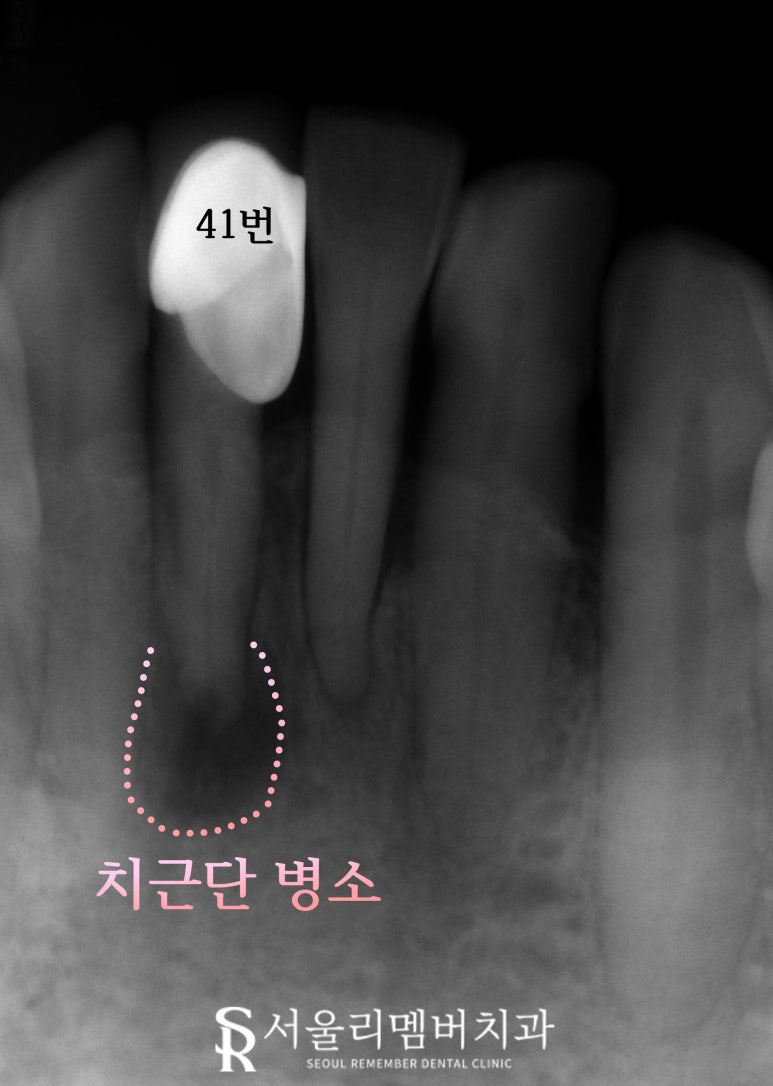

2026.01.04

이 케이스도 약간의 통증이 동반되고 있어

신림 치과 에서 치근단 사진을 촬영해 보니

뿌리 끝부분에 검은 음영이 확인됐습니다.

이 검은 부분이 바로 치근단 병소인데요,

쉽게 말해 치아 뿌리 끝 주변에

세균 감염으로 인한 염증이 쌓여 있다는 의미이죠.

PFM 크라운 하방으로 이차 우식이 생기거나,

내부 밀폐가 불완전해 세균이 침투하면

시간이 지나면서 뿌리 끝까지

감염이 진행될 수 있습니다.